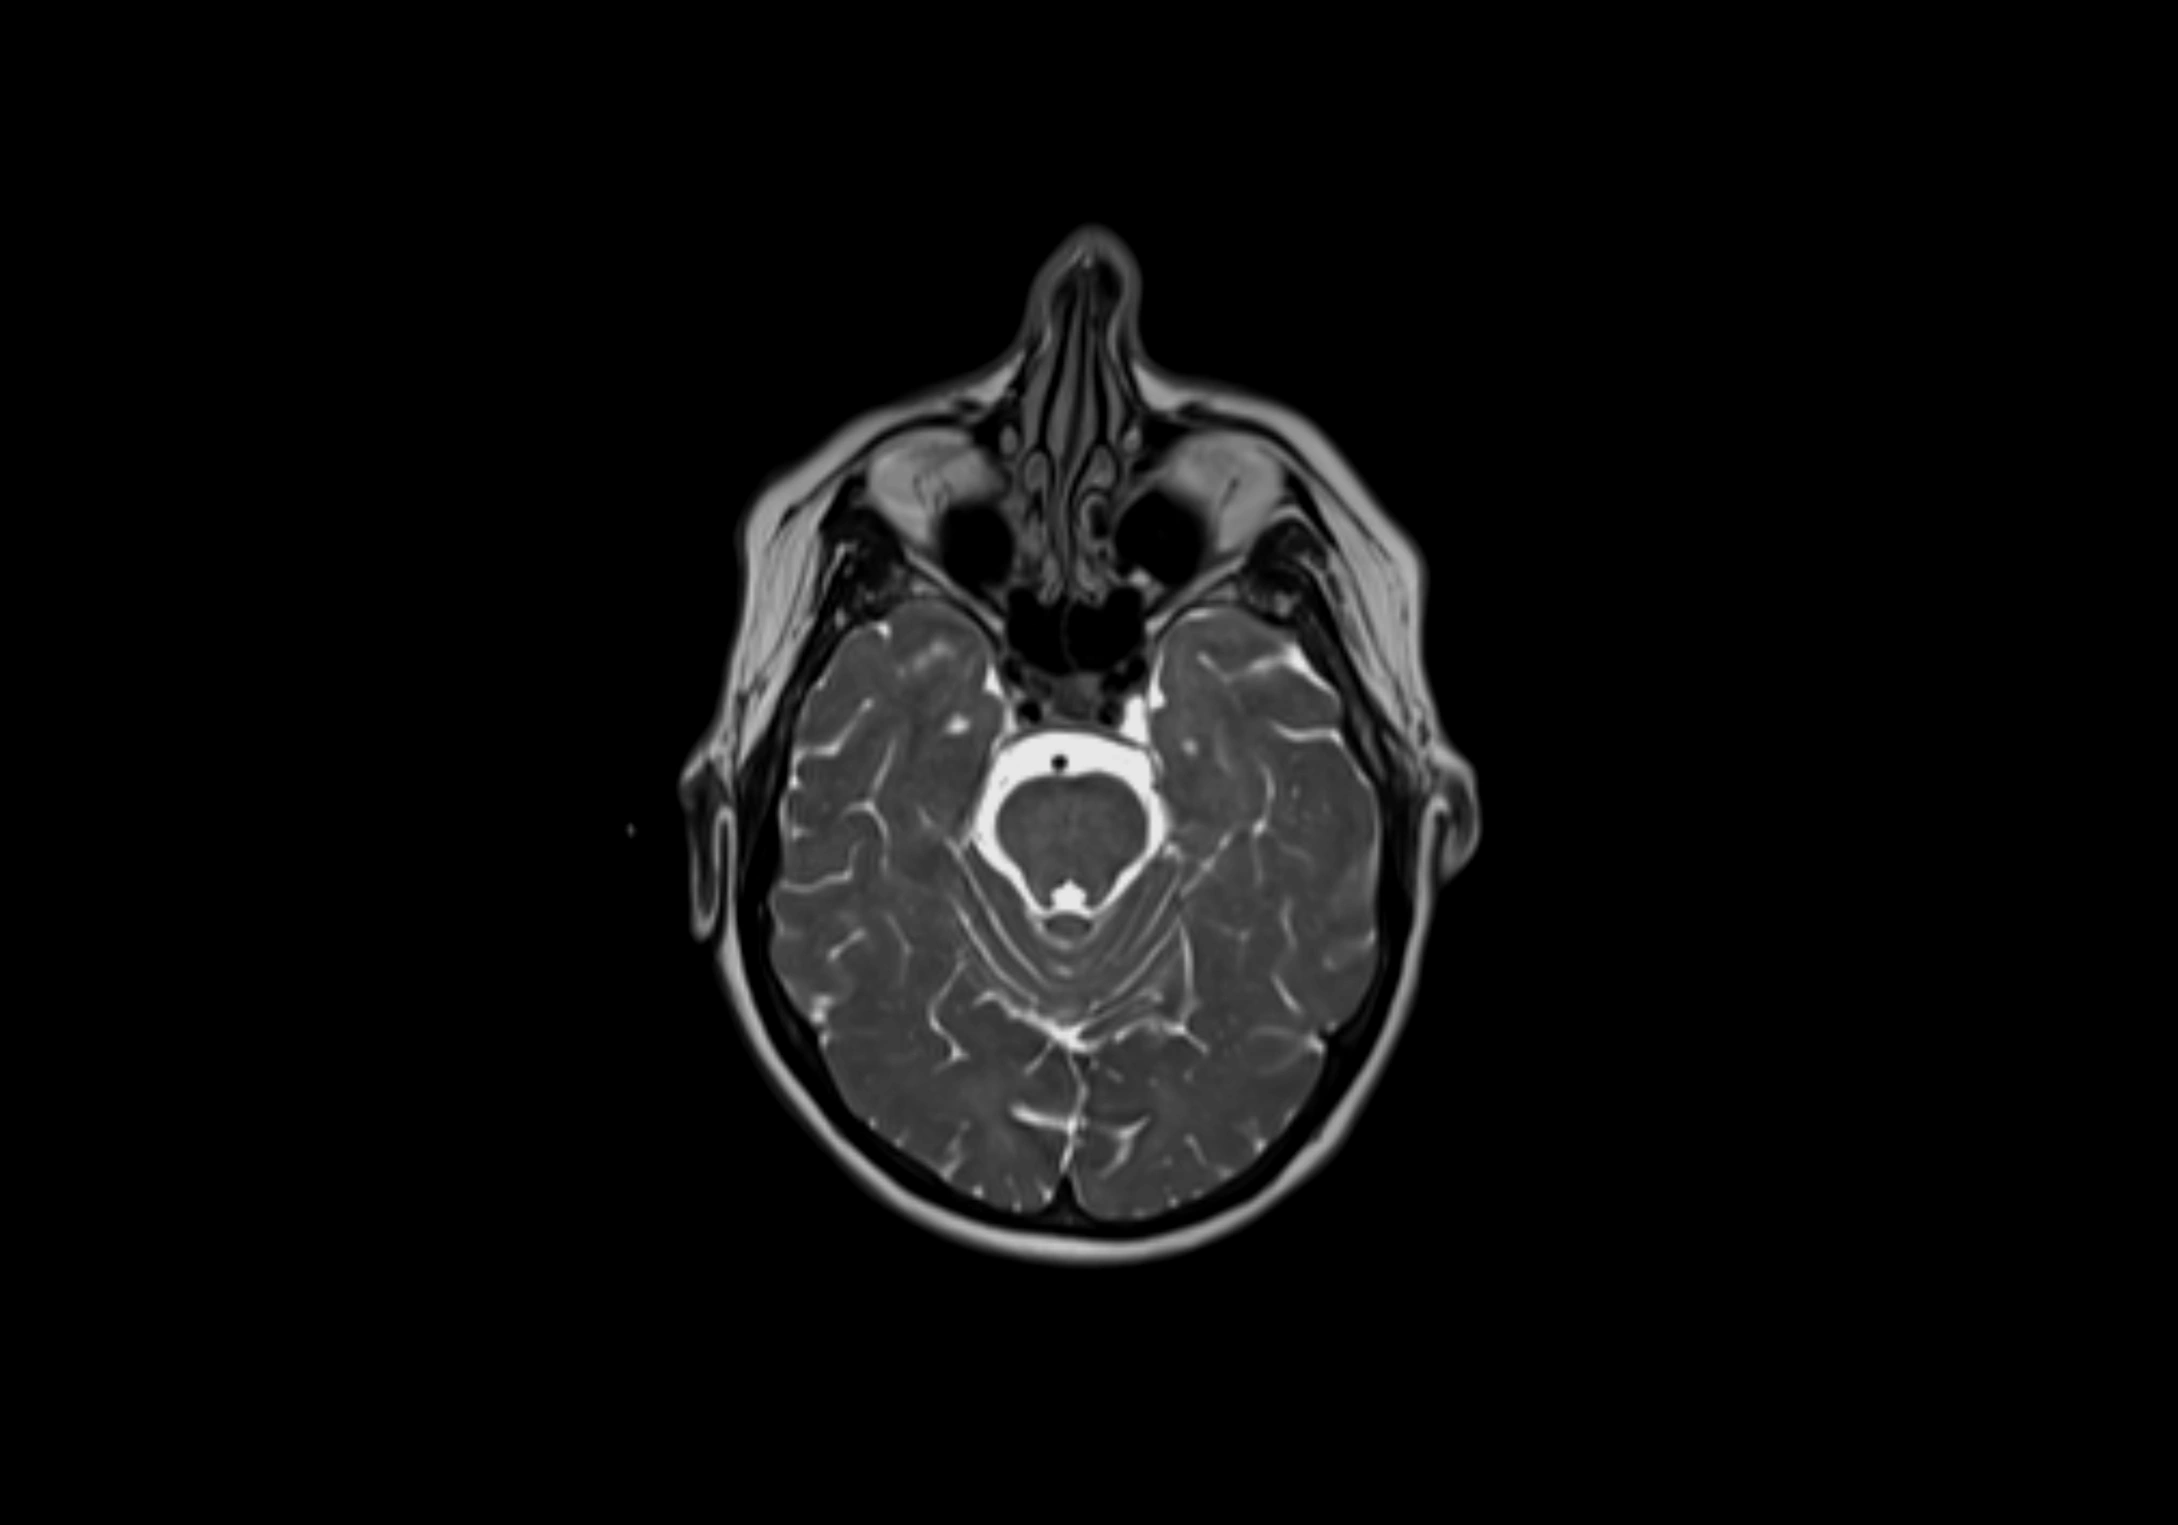

MRI images

image